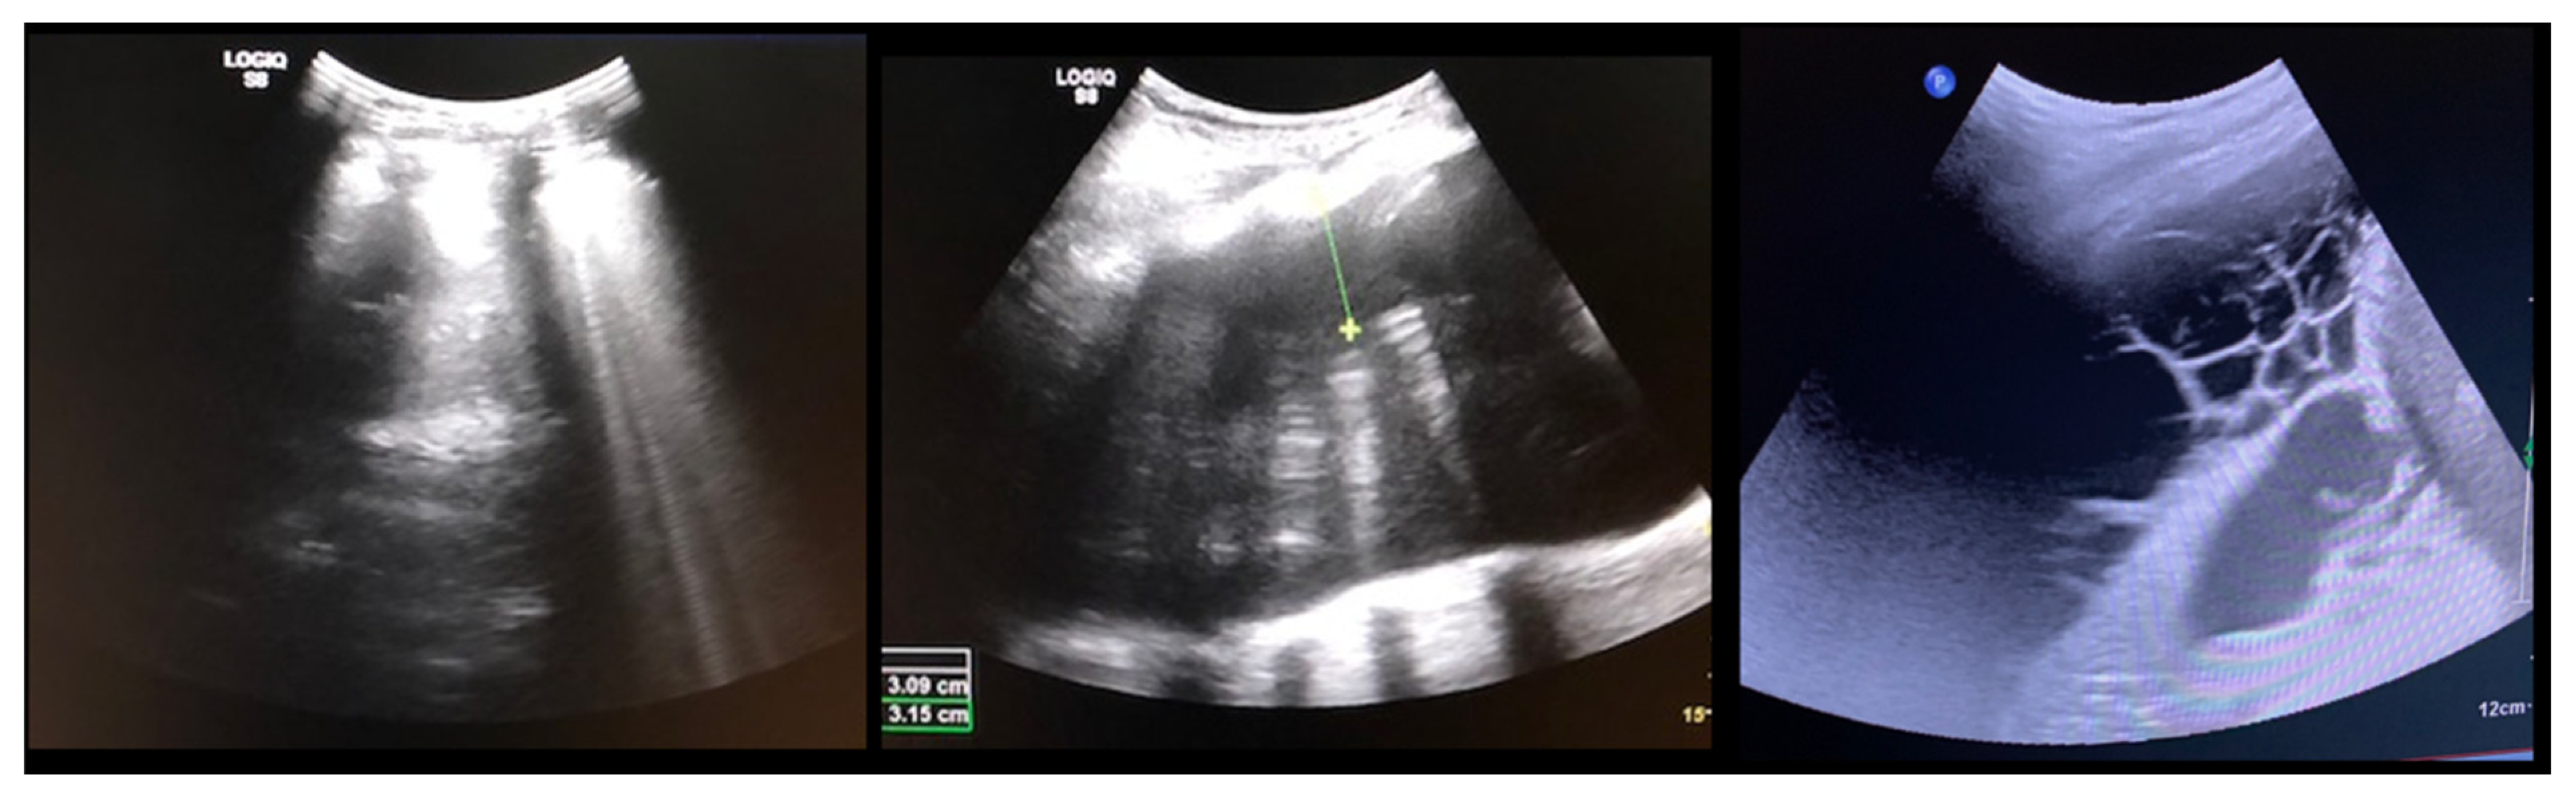

All patients received a postoperative chest tube, one for each side for double instrumentation. The tube was removed once the output decreased to less than 100 mL per 24 h. Once this threshold was reached, as an extra safety measure, we performed ultrasounds to quantify the remaining pleural effusion (Figure 1): the chest-tube was removed if less than 200 mL residual effusion was measured. The patients were monitored at the Intermediate Care Unit (ICU) until the chest tubes were removed.

Figure 1.

(Left) normal pleural ultrasound with the lung-shadow attached to the ribs; (Middle) Pleural effusion shown by a black/empty area between the ribs and the lung tissue; (Right) Cavernous hematoma shown by multiple cystic formations.